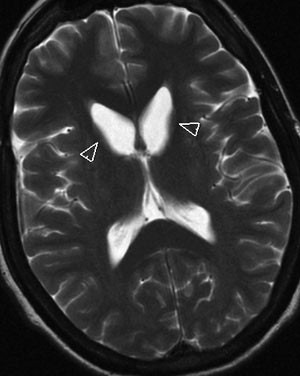

I perifert blodutstryk var det et signifikant økt antall akantocytter. I preparert utstryk etter fire timer hadde pasienten 3,2 % akantocytter, mens det i prøver fra to friske kontrollpersoner var 0 %. Cerebral MR viste lett bilateral atrofi av caput nucleus caudatus (fig 1) og i tillegg en lett grad av sentral og kortikal atrofi, alderen tatt i betraktning. Western blot, utført langt senere, viste totalt fravær av proteinet chorein.

Det er personlighetsendringer – pasienten blir kognitivt svekket og kan ha psykiatriske symptomer i form av trikotillomani, tvangspreget handlingsmønster, AD/HD-liknende symptomer og symptomer som kan minne om Tourettes syndrom. Personlighetsendring kan være debutsymptom. Det kliniske bildet er altså meget heterogent, og det forekommer betydelig fenotypisk variasjon selv innenfor samme familie (9). Bildediagnostisk finner man ofte lett atrofi av nucleus caudatus og av putamen, som ses best i koronalsnitt (10).